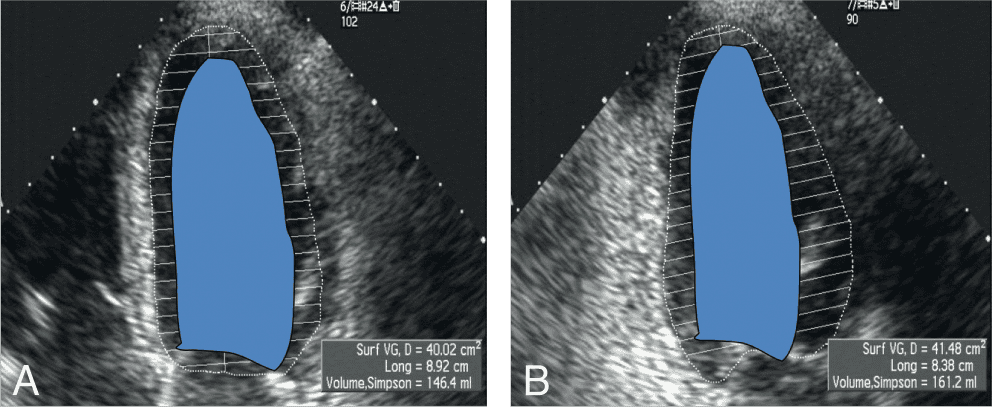

CARDIOLOGIE PÉDIATRIQUE 📌 À LA UNE : Cardiac evaluation of paediatric athletes: A clinical [...]